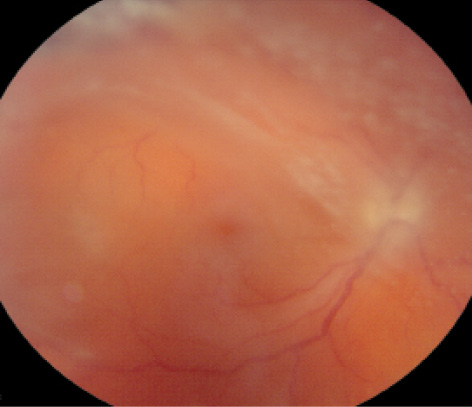

Infectious endophthalmitis is a devastating vision-threatening condition involving inflammation of the entire globe and its intraocular contents (Figure 1). The most common form of infectious endophthalmitis tends to result from direct inoculation of an organism from outside the body (ie, exogenous as opposed to endogenous), most commonly after cataract surgery or intravitreal injection. It tends to present acutely within 3 to 21 days after the procedure.

Figure 1. Postoperative exogenous endophthalmitis presenting as panuveitis. Anterior segment may present with corneal edema, marked anterior chamber cellular reaction, and fibrin inflammatory membrane over the pseudophakic posterior chamber intraocular lens (A). The posterior segment typically has vitritis (seen on echography; B) with retinal hemorrhages.